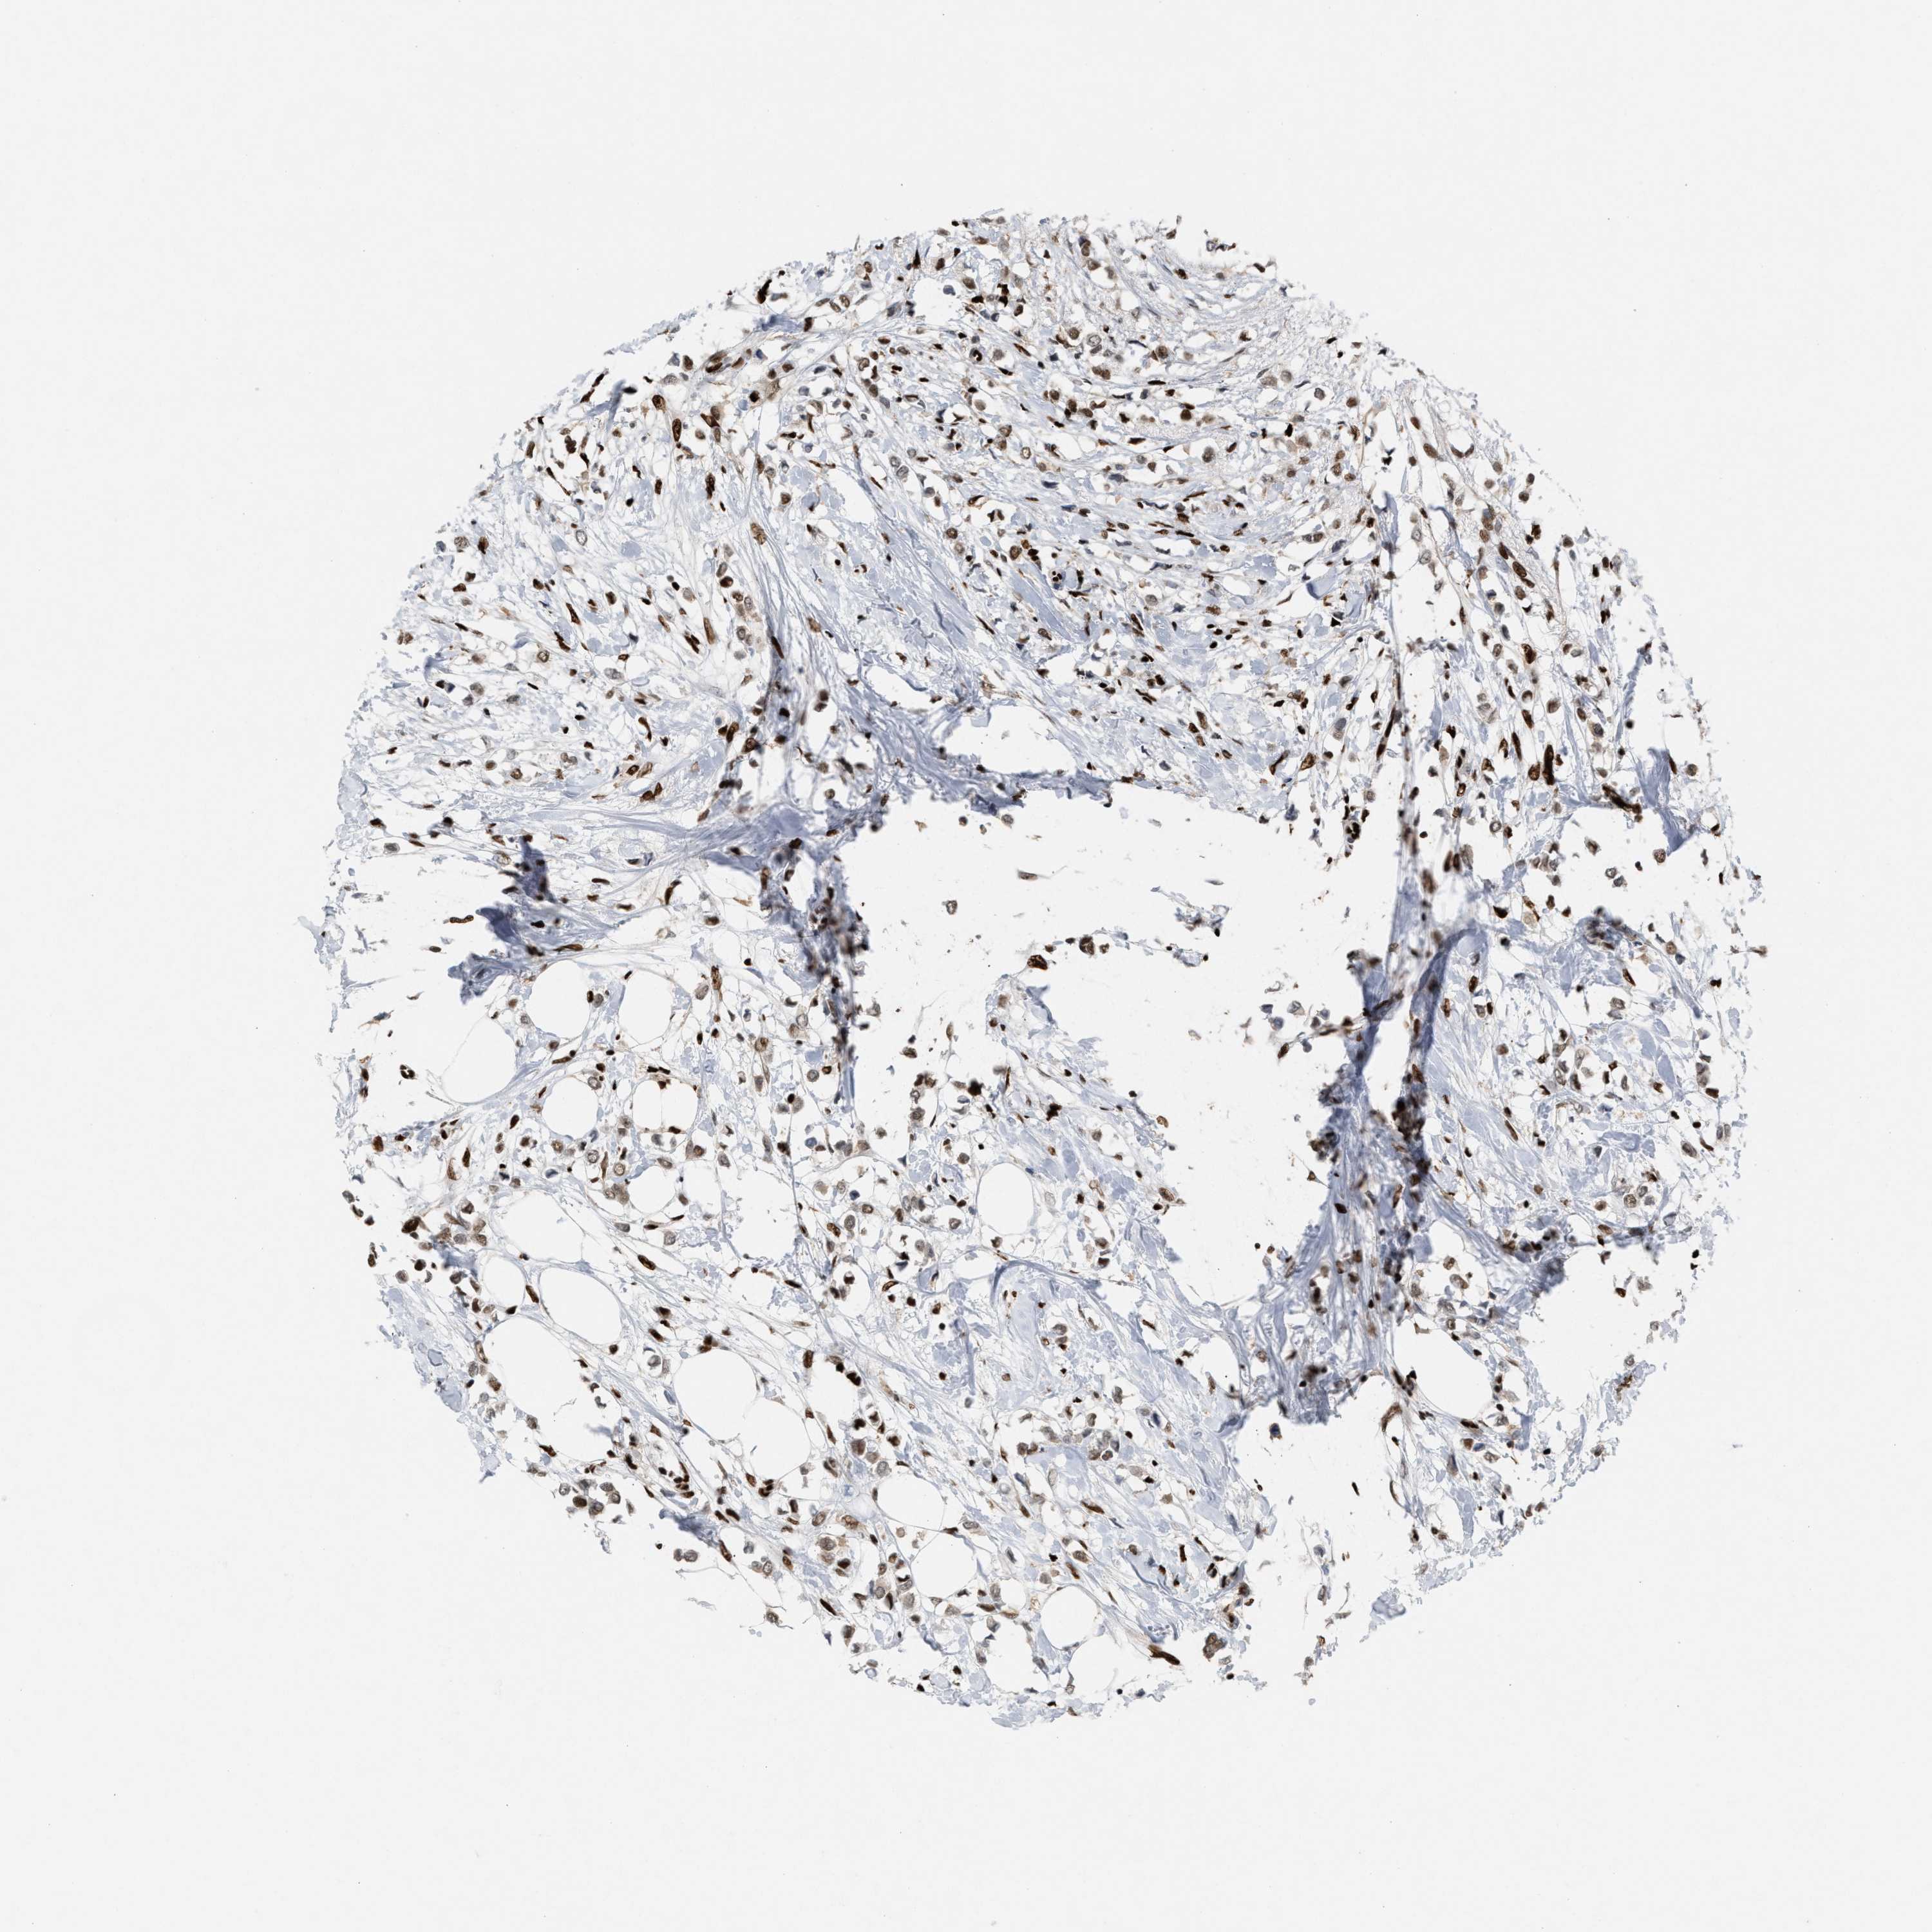

CANCER BREAST CANCER Show tissue menu

BRCA TCGA BRCA VALIDATION PROTEIN EXPRESSION

ANTIBODIES

AND

VALIDATION